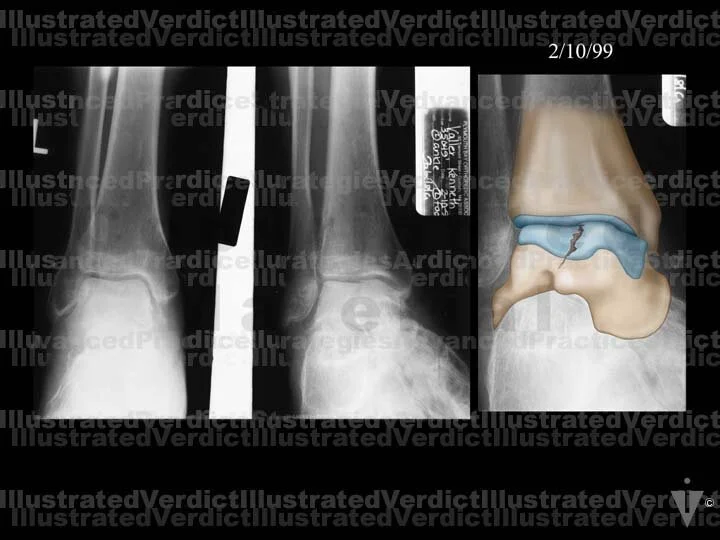

1. Original film

2. Original film with enhanced illustration